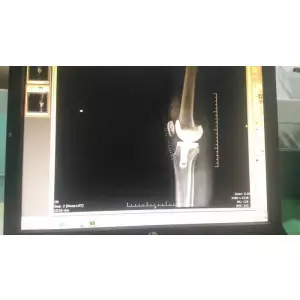

Jay Patel - USA